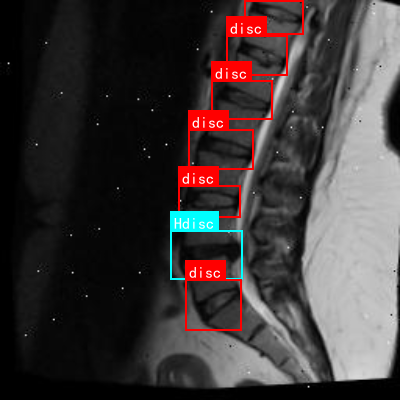

上图展示了一张典型的腰椎MRI矢状位图像,其中标注了正常椎间盘("disc")和异常椎间盘("Hdisc")。通过对比这些标注,我们的模型可以学习到正常与异常椎间盘之间的差异,从而实现准确的检测与分类。

上图展示了不同模型在腰椎间盘突出分割任务上的可视化结果对比。可以看出,基于HRNet的模型能够更准确地分割出突出的椎间盘区域,边界更加清晰,特别是对于小范围的突出,分割效果明显优于其他模型。